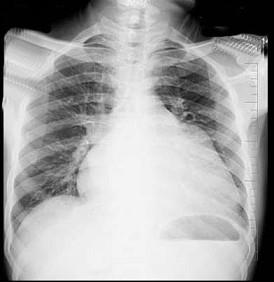

问题 56岁男性患者,劳累后心慌气促10余年,近来自觉症状加重。临床听诊,心尖区有舒张期隆隆样杂音,行胸部X检查,如图所示,你认为下列描述正确的是 ( )

选项 A、考虑三尖瓣狭窄 B、右前斜位示左心房增大,心后上缘后突压迫冲钡食管 C、左前斜位示心影向后下方突出 D、考虑二尖瓣狭窄

答案 BCD